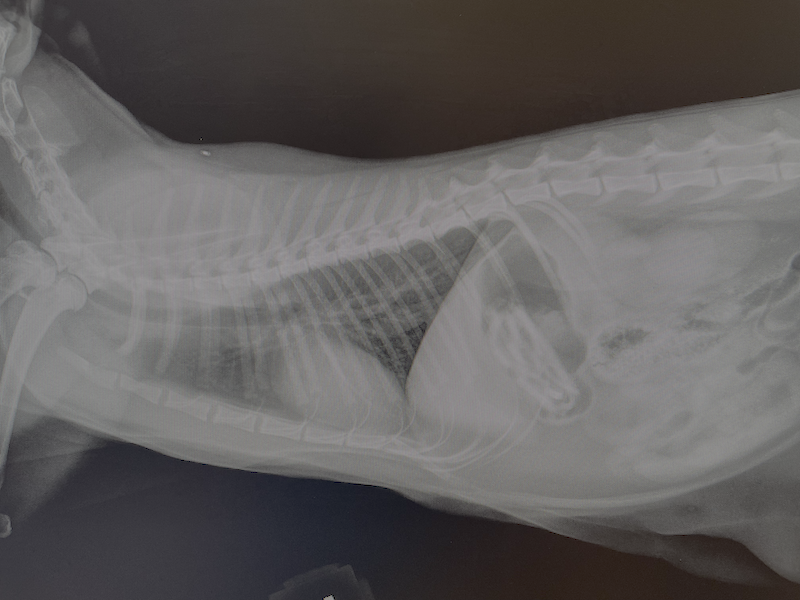

I write this from the veterinary hospital. My one-year-old cat Twiggy ate a dozen hair ties last night while we were at a friend’s house celebrating NYE. Alas, what an omen for 2026. I am almost certain that she’ll be ok. She’s always been our little diva, and now I have the vet bill to prove it.